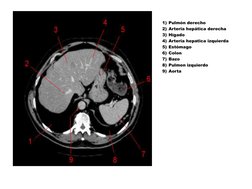

Pulmn derecho

Arteria heptica derecha

Hgado

Arteria hepatica izquierda

Estmago

Colon

Bazo

Pulmon izquierdo

Aorta